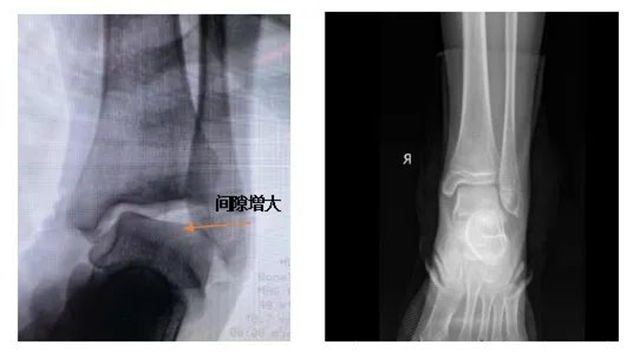

◆ 慢性踝关节不稳影像学检查可见:胫骨倾斜,间隙增大(左图);正常踝关节胫距关节呈平行界面,胫距间隙正常(右图)。